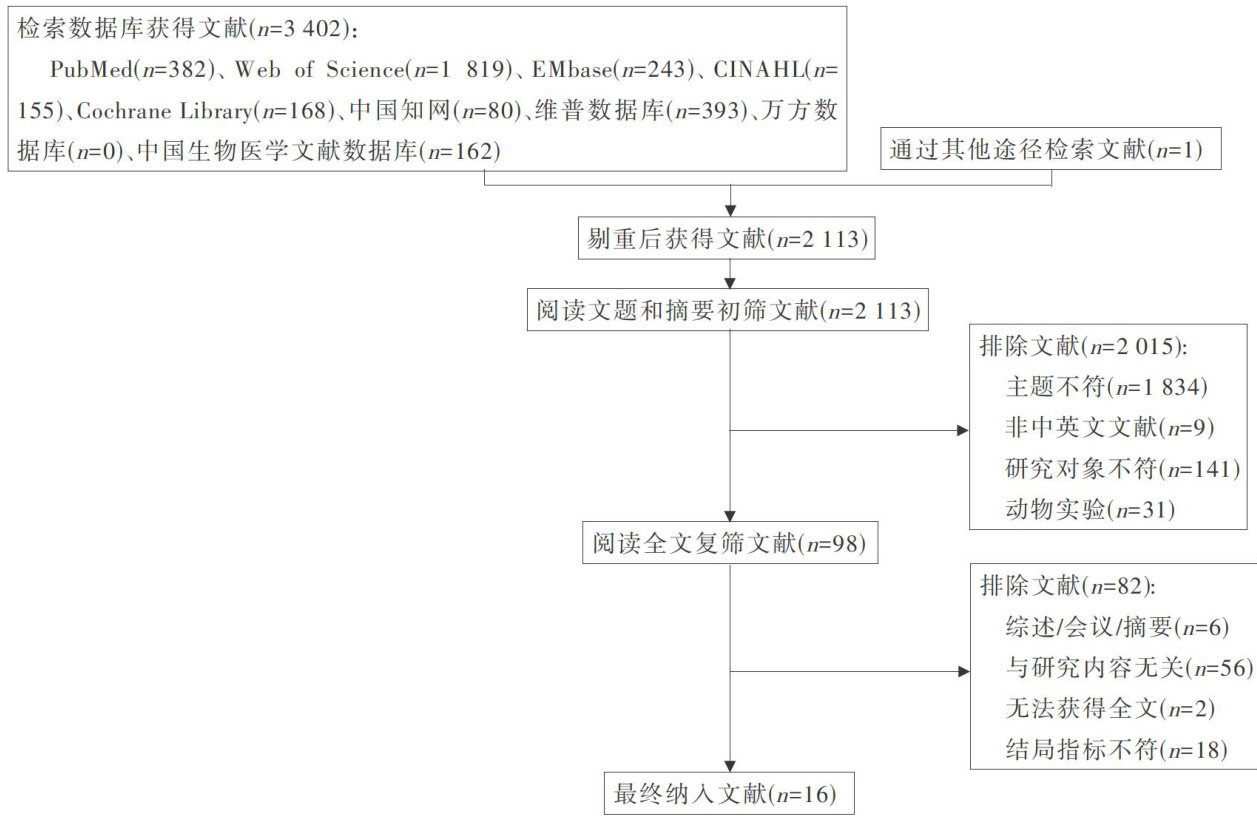

科研论著 | 不同浓度盐水鼻腔冲洗对慢性鼻窦炎内镜术后治疗有效性的网状Meta分析

科研论著 | 不同浓度盐水鼻腔冲洗对慢性鼻窦炎内镜术后治疗有效性的网状Meta分析